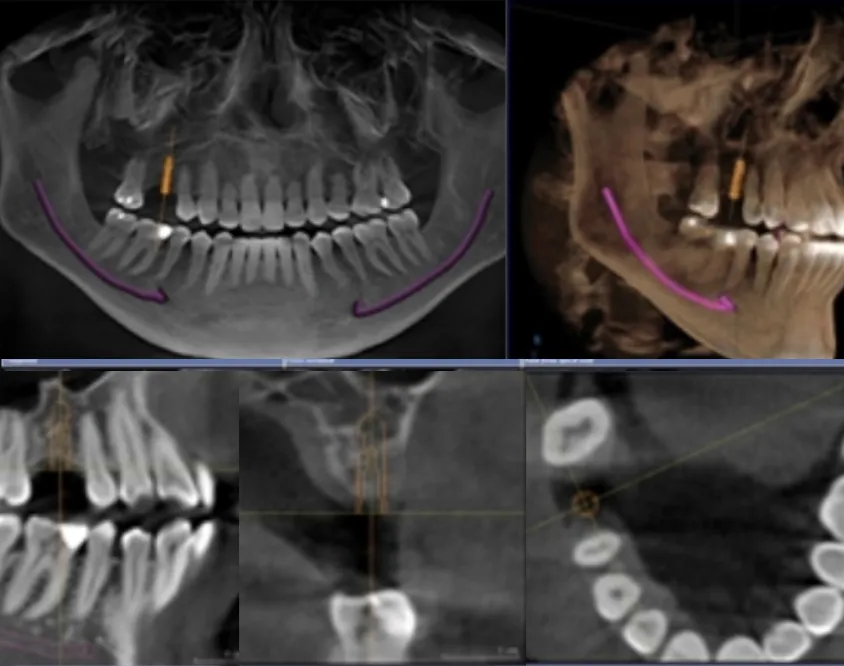

CBCT 3D Imaging

3D imaging provides dr. Justina with highly detailed images of your teeth. The technology we use provides images of your jaw bone, airways, nerves, blood vessels, and soft tissues, too, providing a far more comprehensive picture of your oral health.

CBCT 3D Imaging

3D imaging provides dr. Justina with highly detailed images of your teeth. The technology we use provides images of your jaw bone, airways, nerves, blood vessels, and soft tissues, too, providing a far more comprehensive picture of your oral health.